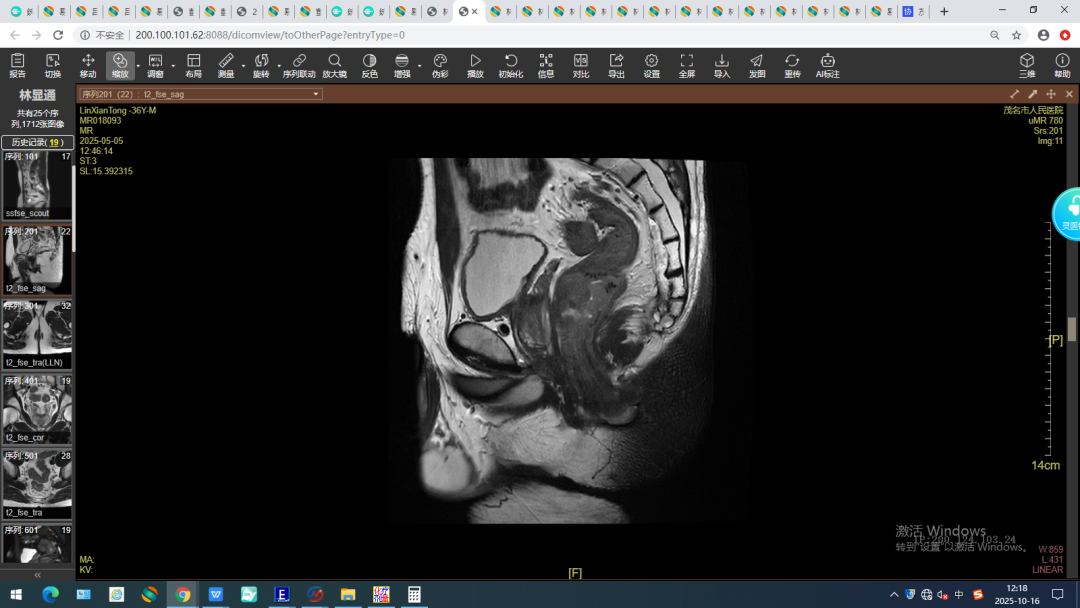

2024年10月,林先生(化名)偶然间发现自己大便带血、伴粘液及形状变细,但并没有引起重视。直到这样的症状持续了半年之久,他才来到了茂名市人民医院消化内科门诊就诊。经全腹CT及直肠高分辨MR增强检查提示,一个直肠病灶已悄然生长,如同埋在体内的“定时炸弹”,后续病理活检确诊为直肠腺癌,临床分期为cT3N2bM0 ⅢC期。如继续拖延下去,患者很可能会有生命危险!

(治疗前)